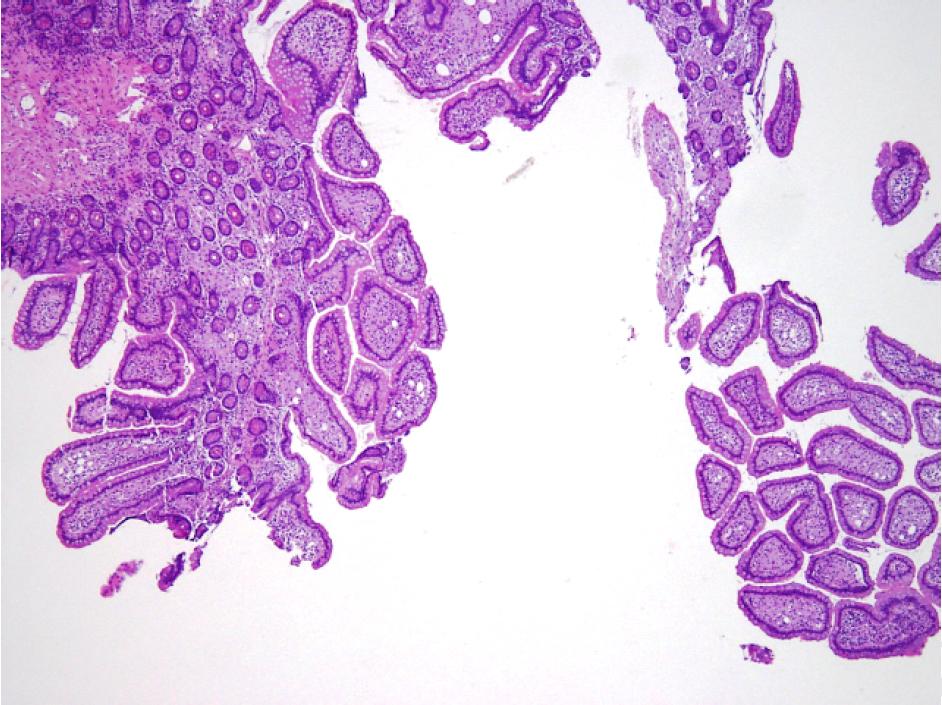

病理组织学检查结果显示,黏膜固有层和黏膜下层均有弥漫性泡沫状巨噬细胞的浸润,周围淋巴管扩张(图D,箭头;苏木精伊红染色;原始放大倍数,x 40)。

图D